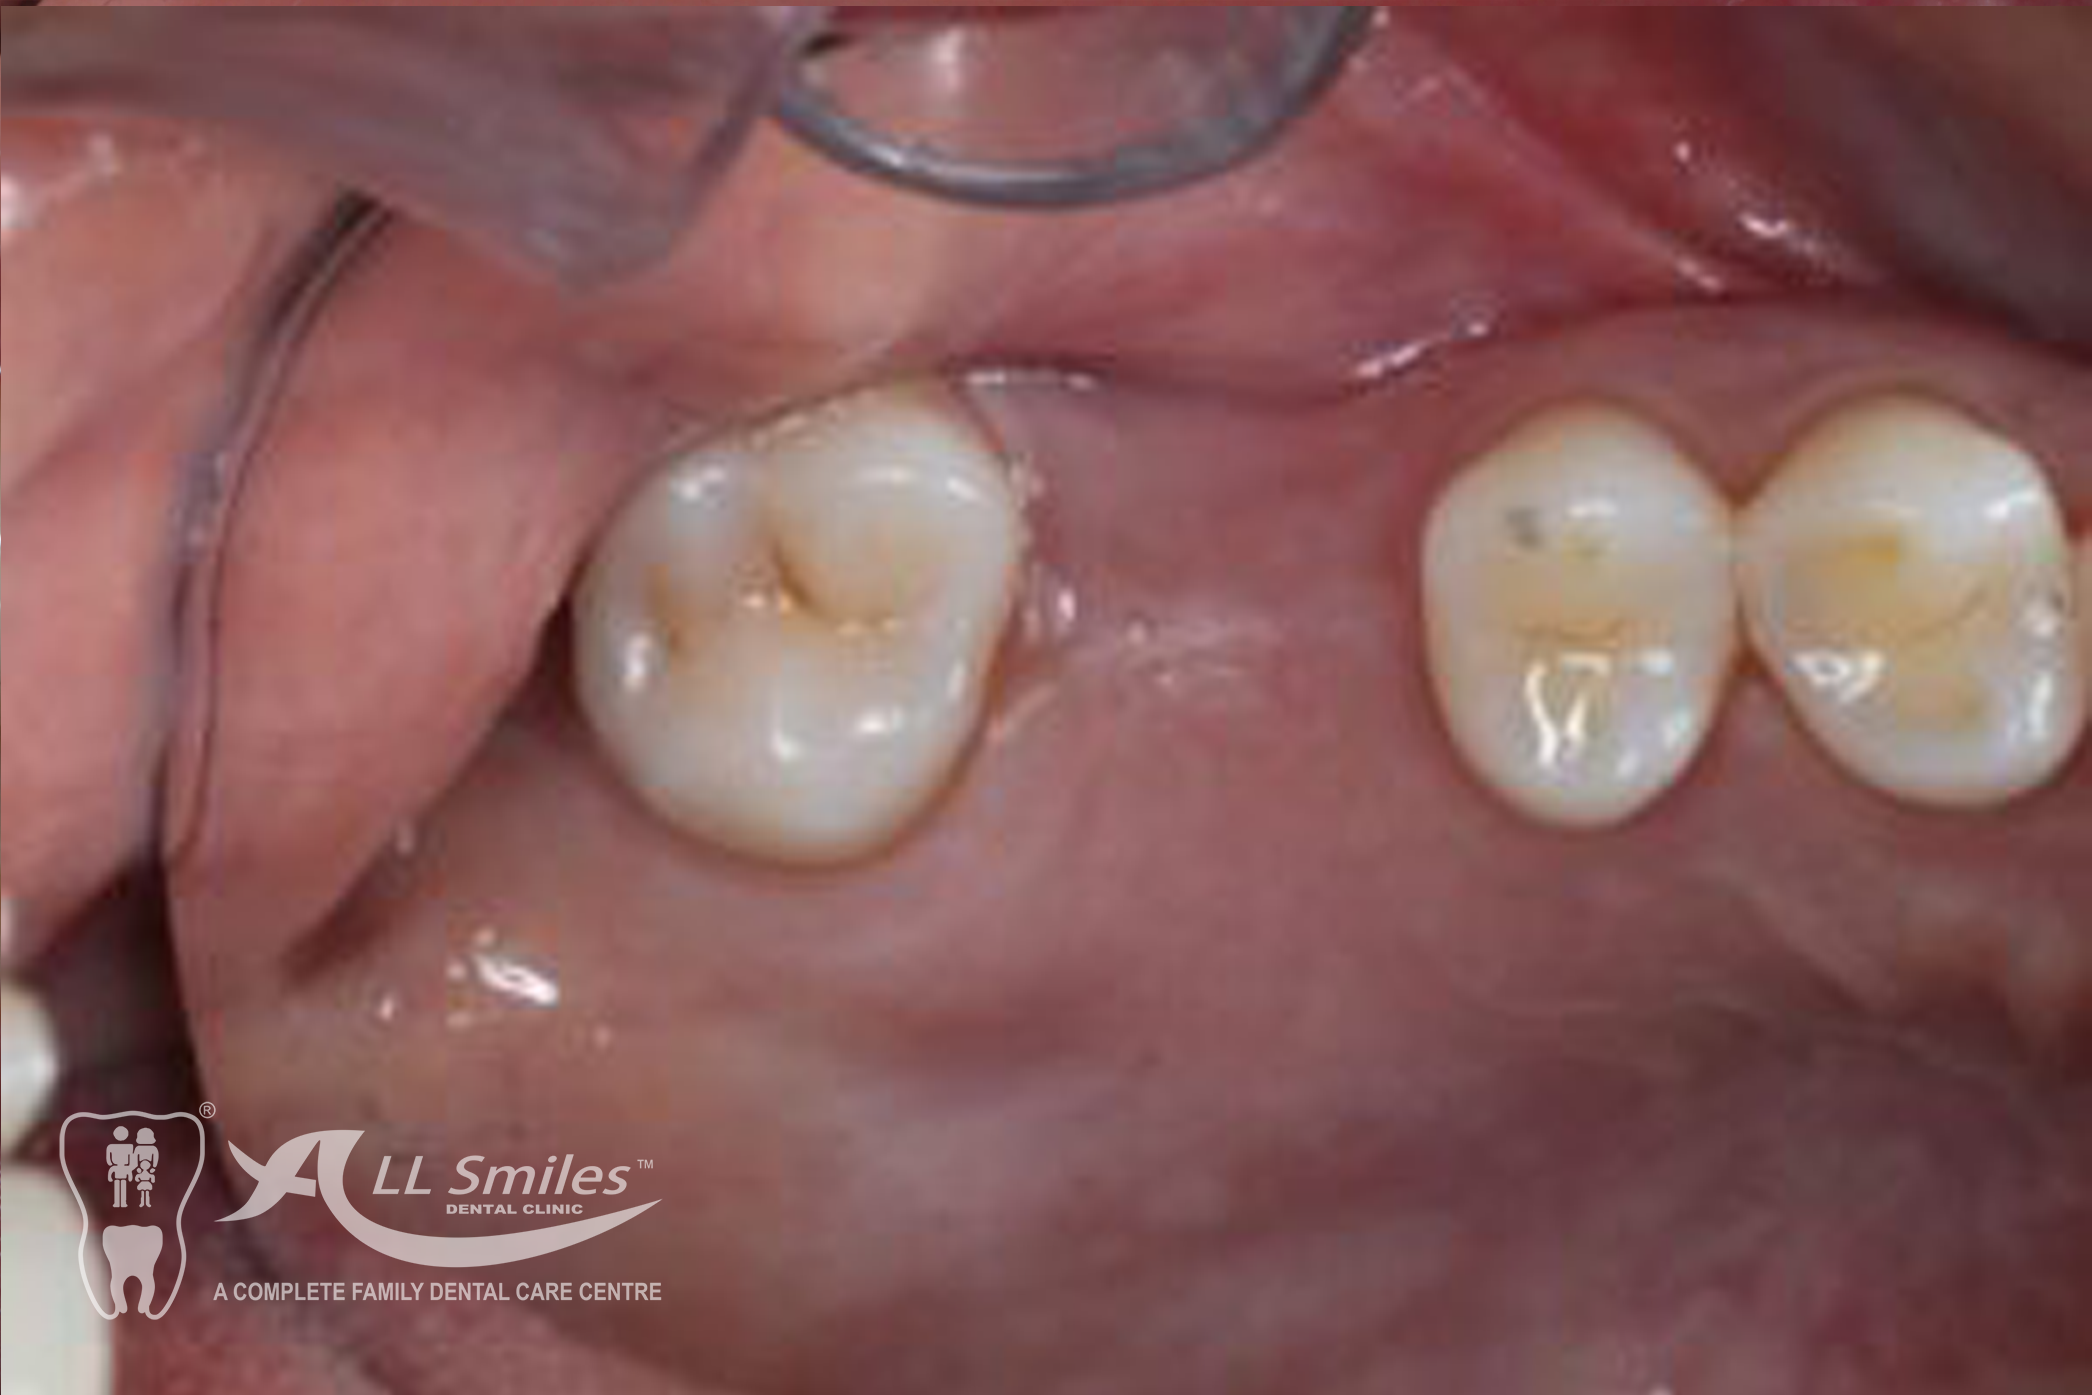

Dental Implants Gallery